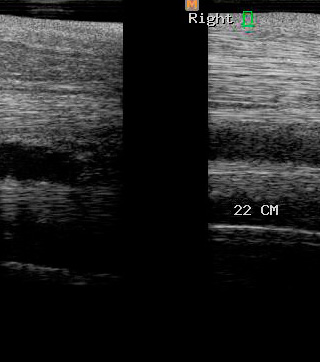

Ecografía

Cuenta con Ecografía digital de alta complejidad.

17 años de experiencia siendo una de las ecografistas más reconocidas en la práctica de equinos. Realiza pasantías en la universidad de Davis California y en Mid-Atlantic Equine Medical Center en New Jersey.